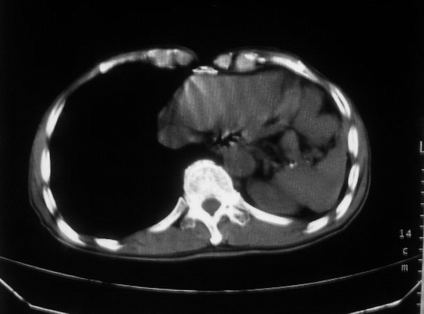

男,66岁,贲门ca术后一年,喝了5、6杯水了。怎么描述跟诊断啊